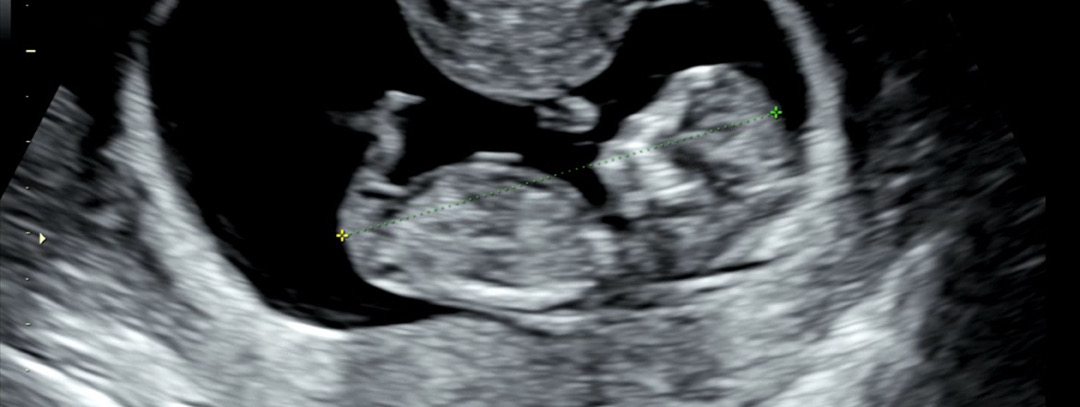

아들일까요? 딸일까요? 한번만 봐주세요! 🙏🏻

의사선생님의 의견과 각도법+챗gpt의 의견이 달라요 저 튀어나와있는 부분이 생식기인걸까요? 생각보다 길어보여서... 투표 부탁드립니다❤️

어차피 각도법볼때는 다 튀어나와있대요